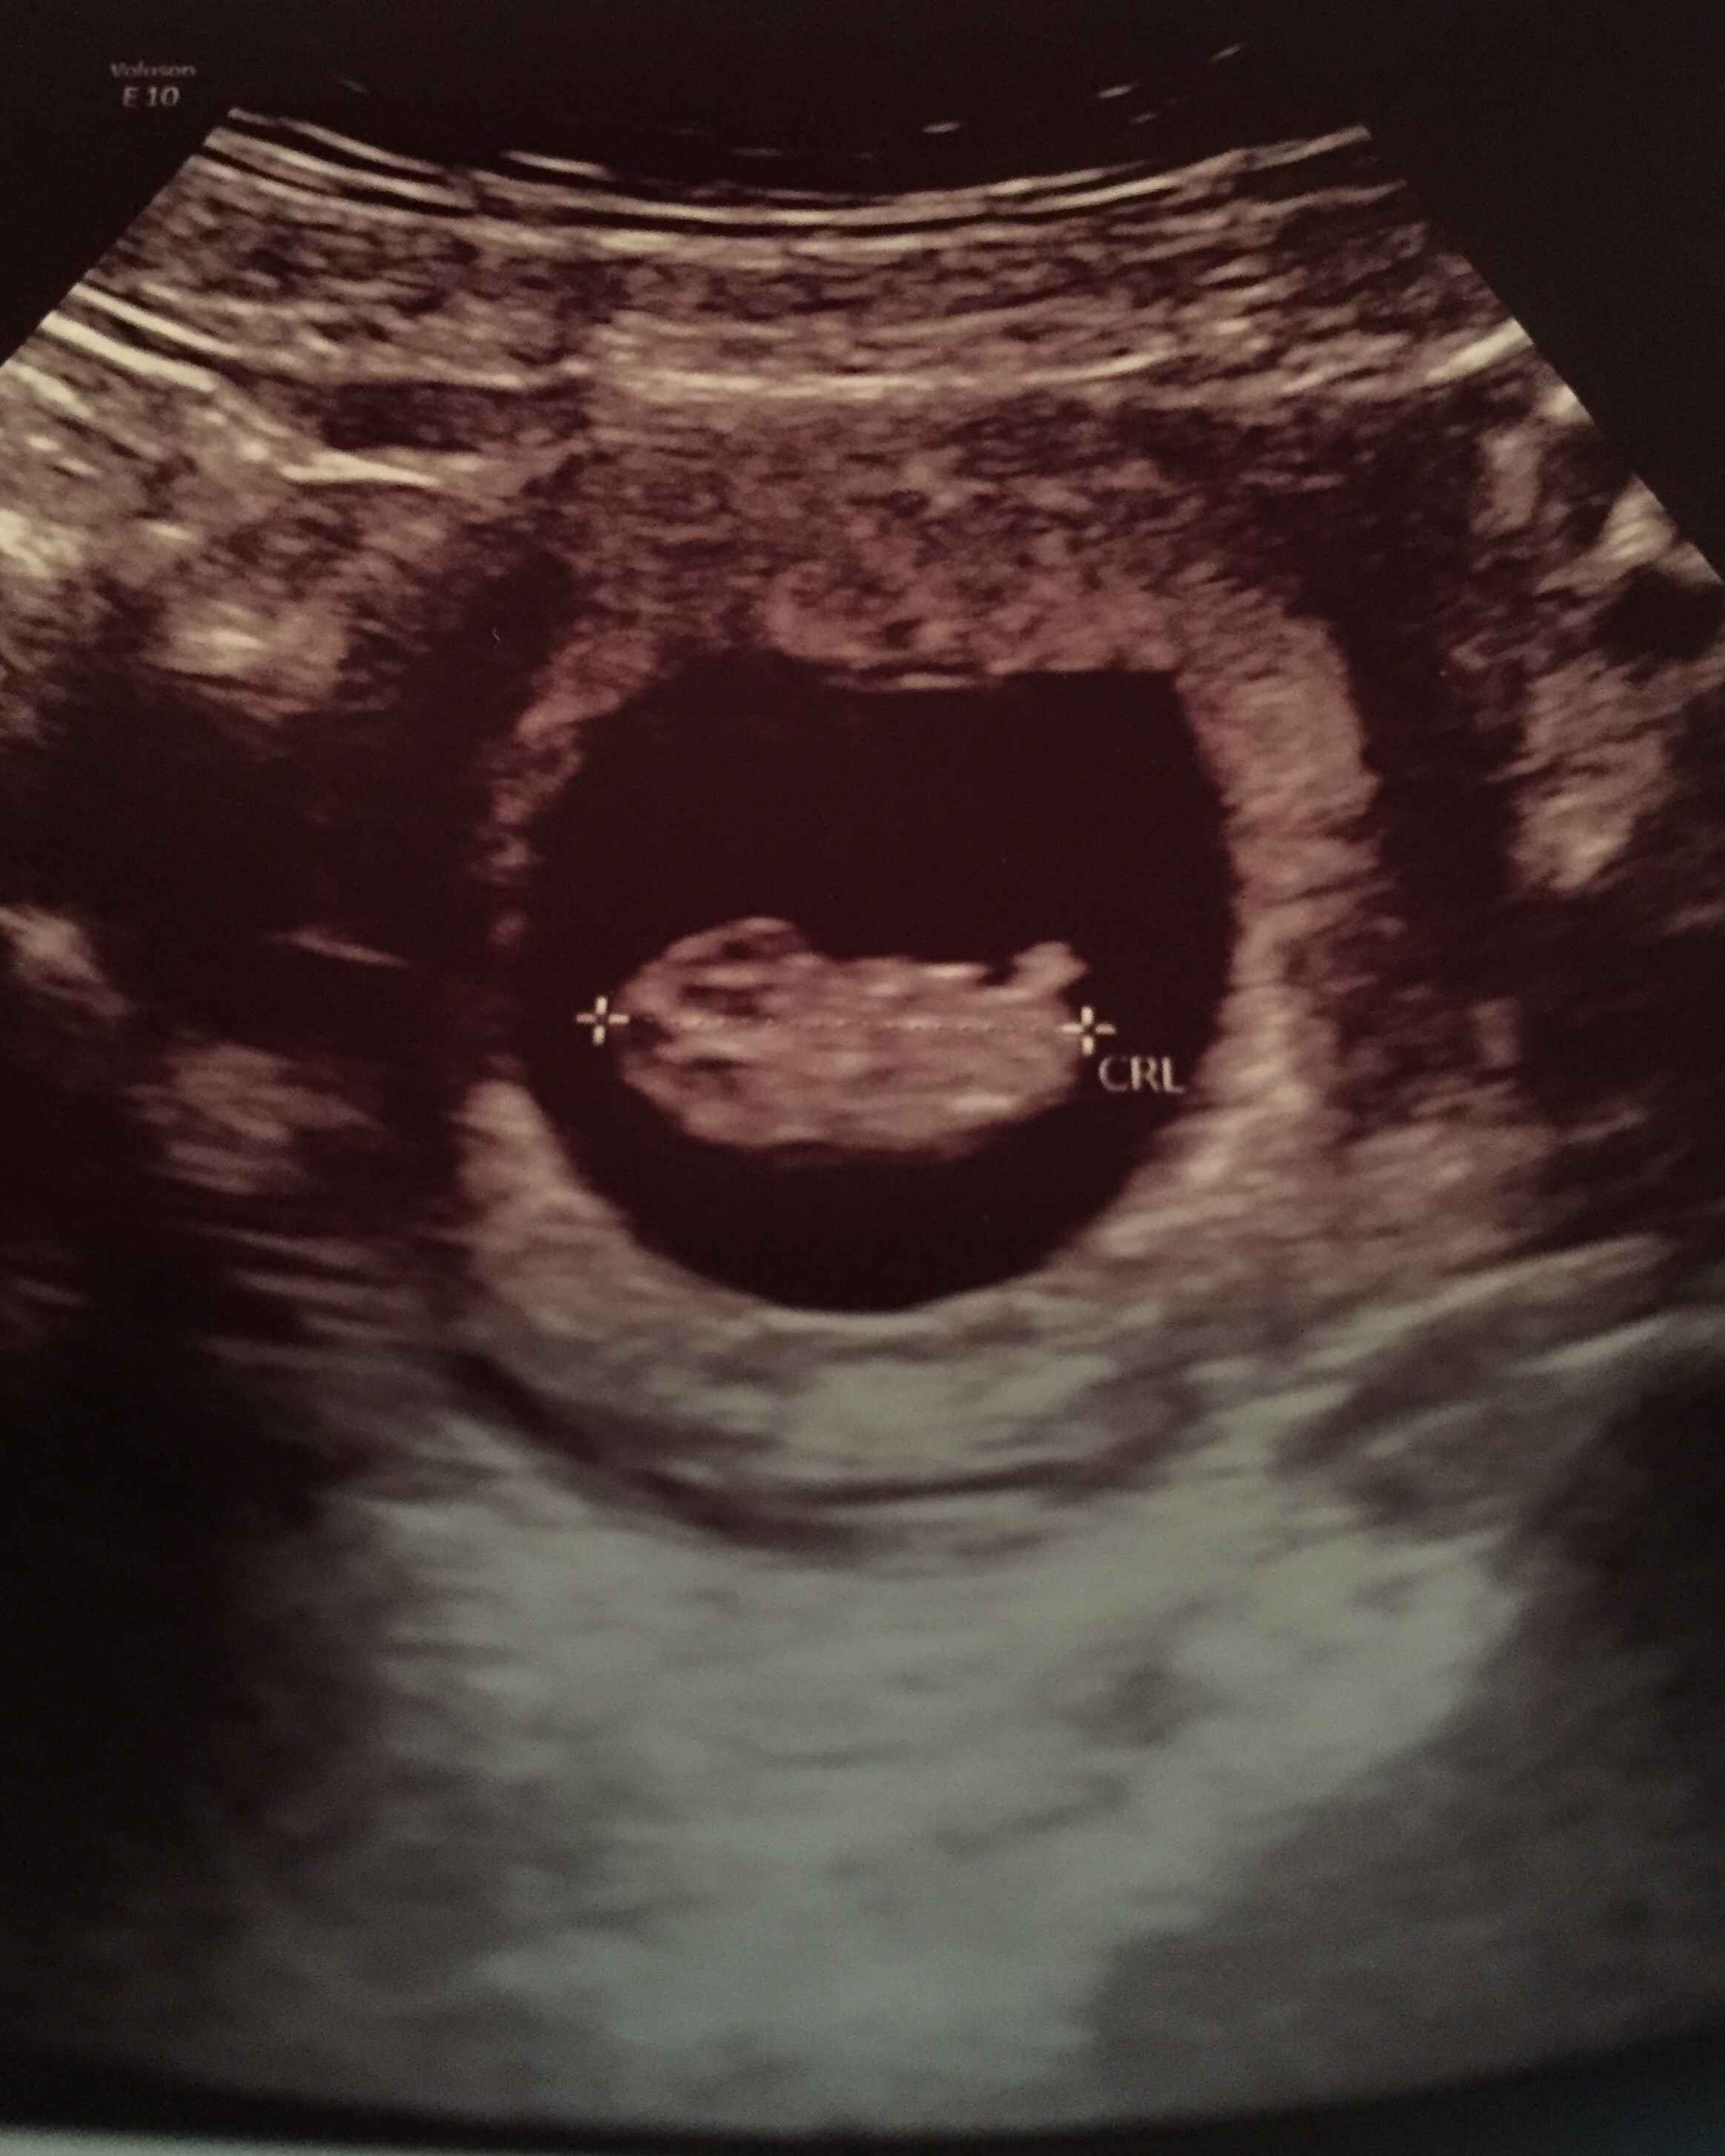

• Here's our nugget measuring at 10 weeks, 6 days. He or she was wiggling and swimming all around when we were watching the screen. So cool!! Heartbeat of 163 BPM. :) Feeling very blessed!